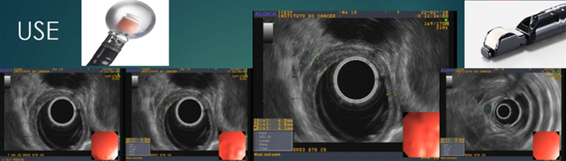

Portanto, é muito importante definir a profundidade da lesão na parede esofágica. O exame endoscópico minucioso com aparelho de luz branca em alta definição sugere lesão superficial quando a distensibilidade do órgão está preservada, não há úlcera e nem estenose da luz. Diante dessa possibilidade, o ultrassom endoscópico (USE), com uso de probe radial, é o exame de eleição, capaz de determinar a profundidade da lesão na parede do órgão ao mesmo tempo em que permite vasculhar as adjacências à procura de linfonodos suspeitos2. Quanto maior a frequência dos ultrassons utilizados, maior o número de camadas observadas na parede do órgão e maior a acurácia do estadiamento T. Já para a avaliação dos linfonodos (N), sabe-se que a punção com agulha de todo gânglio suspeito com tamanho superior a 10mm também colabora para o aumento na acurácia, principalmente se houver patologista disponível para acompanhar as punções na sala de exames.

Figura 5 - ultrassom endoscópico identificando espessamento da parede esofágica e linfonodo perilesional.